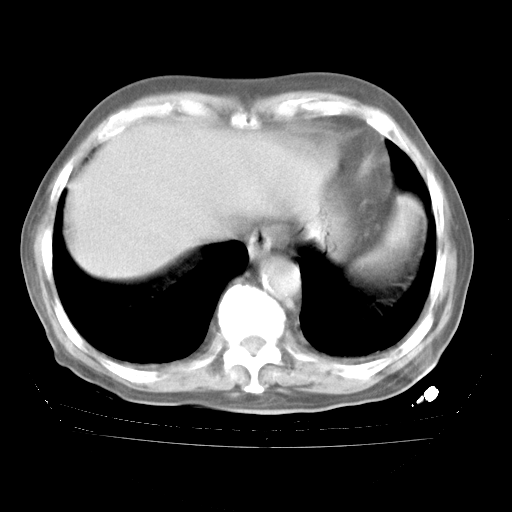

今天部分检查

轻微咳嗽,无痰,(体温正常时)R20次/分,P75次/分,双肺底、腋下可闻及少量捻发音。下肢轻度浮肿。

血常规:白细胞9.11×109/L,N0.92,L5.64,血小板39.2×109/L,HB148g/L,ESR2mm/H。

尿常规:潜血+

血生化:总蛋白69.71g/L,白蛋白38.40g/L,球蛋白31.31g/L,CRP27.9mg/L,尿素氮11.98mmol/L,肌酐106μmol/L,乳酸脱氢酶1099 U/L,肌酸激酶108U/L,CK-MB 61U/L。

腹部B超:胆囊壁增厚,肝、胆、胰、脾、肾无异常,肠系膜淋巴结、腹膜后淋巴结无增大。

ECG:右心室增大

心脏超声检查:无右心室增大。

增加治疗:异烟肼、利福平、乙胺丁醇,静滴左氧氟沙星、参麦注射液。甲强龙从80mg暂减为40mg。

强的松3月1日改为10mg qd,4月1日改为10mg qod。3月份以前的减量过程和环磷酰胺疗程需等明天查看记录(我岳父自己做的记录在他家里)。